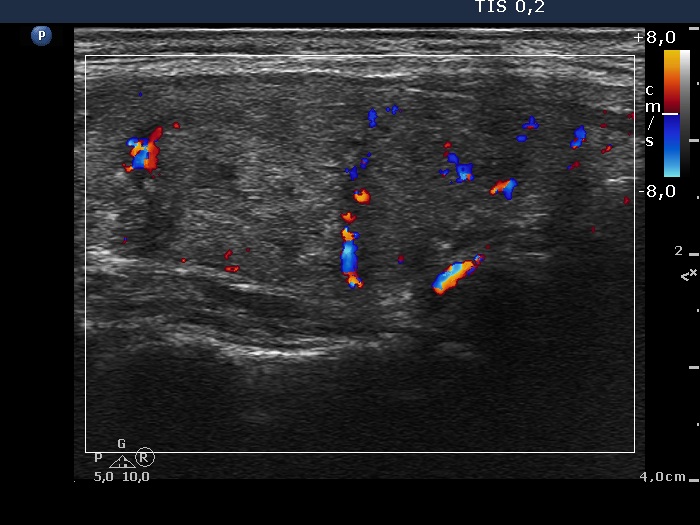

Ultrasonography. The thyroid was echonormal. There were multiple nodules in both lobes including one containing hypoechogenic areas and hyperechogenic granules corresponding to microcalcifications.